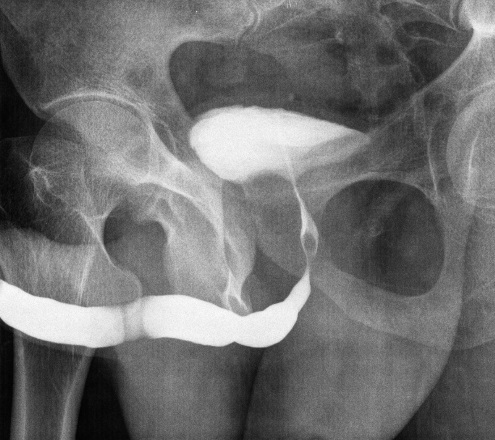

A urethral stricture narrows the urine channel, causing weak stream, straining, infections, or urinary retention. Evaluation with uroflowmetry, urethrogram, and endoscopy defines length, location, and severity. Short, first-time strictures may respond to endoscopic internal urethrotomy (DVIU); long/recurrent ones need urethroplasty for durable cure.

- Excision & primary anastomosis for short bulbar strictures.

- Buccal mucosa graft urethroplasty for longer segments—reliable width using inner cheek graft.